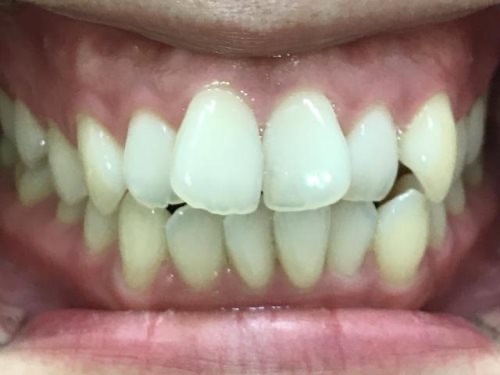

30代女性「ガタガタの前歯と口元の突出感が気になる」マウスピース型矯正装置「インビザラインフル」を使い、非抜歯で歯並びと噛み合わせを改善した症例

「ガタガタの前歯と、口元の突出感が気になる」と、ご相談いただきました。

拝見すると、上下左右の前歯12本(中切歯/1番・側切歯/2番・犬歯/3番)がでこぼこに生えている「叢生(そうせい)」でした。

歯並びがきれいに整い、見た目と噛み合わせが改善しました。